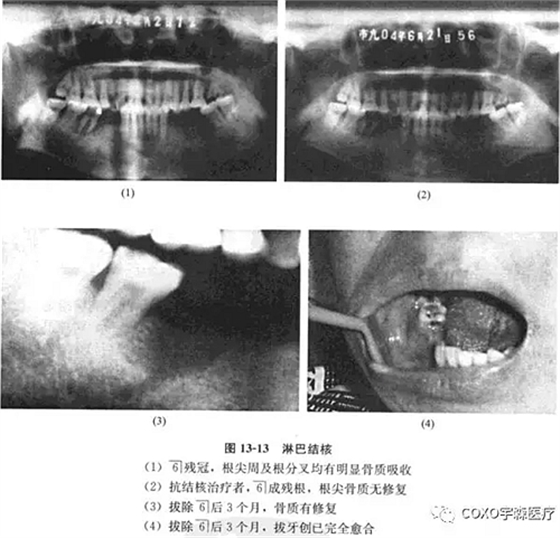

檢查:7-3]牙齦腫脹,54]缺失,6]呈殘冠狀,近中齦有炎性肉芽組織。x線片示:6]殘冠,根尖周及根分叉均有明顯骨質(zhì)吸收,雙頜下淋巴結(jié)腫大,質(zhì)中偏硬,臨床診斷為6]根尖周炎,頜下淋巴結(jié)核可能。

經(jīng)右頜下淋巴結(jié)穿刺,見上皮細(xì)胞、多核巨細(xì)胞和淋巴細(xì)胞,結(jié)合臨床及6]近中原切片,認(rèn)為病變符合結(jié)核診斷。行抗結(jié)核治療,3個月后復(fù)查,臨床頜下淋巴結(jié)顯著縮小,口內(nèi)牙齦腫脹基本消失,無任何創(chuàng)面,殘冠已折斷,僅剩6]殘根,X線示根尖周骨質(zhì)無修復(fù)現(xiàn)象。遂拔除司殘根,繼續(xù)行抗結(jié)核治療,3個月后骨質(zhì)有修復(fù),拔牙創(chuàng)已完全愈合(圖13-13)。

結(jié)核病可出現(xiàn)在口腔軟組織,也可以出現(xiàn)在頜骨組織內(nèi),臨床不多見。結(jié)核病出現(xiàn)在軟組織時可表現(xiàn)為潛穴性潰瘍,疼痛癥狀十分顯著。本病例最初表現(xiàn)為牙痛及牙齦腫塊,6]為死髓牙, 線片示根尖骨質(zhì)有吸收,牙齦組織切片僅提示結(jié)核可疑;后經(jīng)下頜下淋巴穿吸活檢6]區(qū)病損亦確認(rèn)為結(jié)核。經(jīng)抗結(jié)核治療后逐步好轉(zhuǎn),口內(nèi)腫脹消失,拔除6]后骨質(zhì)也逐漸得以修復(fù)。

本病例十分不典型,無疼痛癥狀;局部又存在死髓牙,極易誤診為根尖周病。其最后診斷依賴于下頜下淋巴結(jié)病理檢查,提示在診治根尖周病時必須進(jìn)行全面的口腔頜面部檢查而不僅僅限于牙及牙槽部。

本例6]根尖周病由殘冠引發(fā),局部伴發(fā)結(jié)核,髓腔通道可能是感染途徑之一。綜上所述,根尖周疾病的鑒別診斷,除特殊情況外,一般也并不困難,關(guān)鍵是: